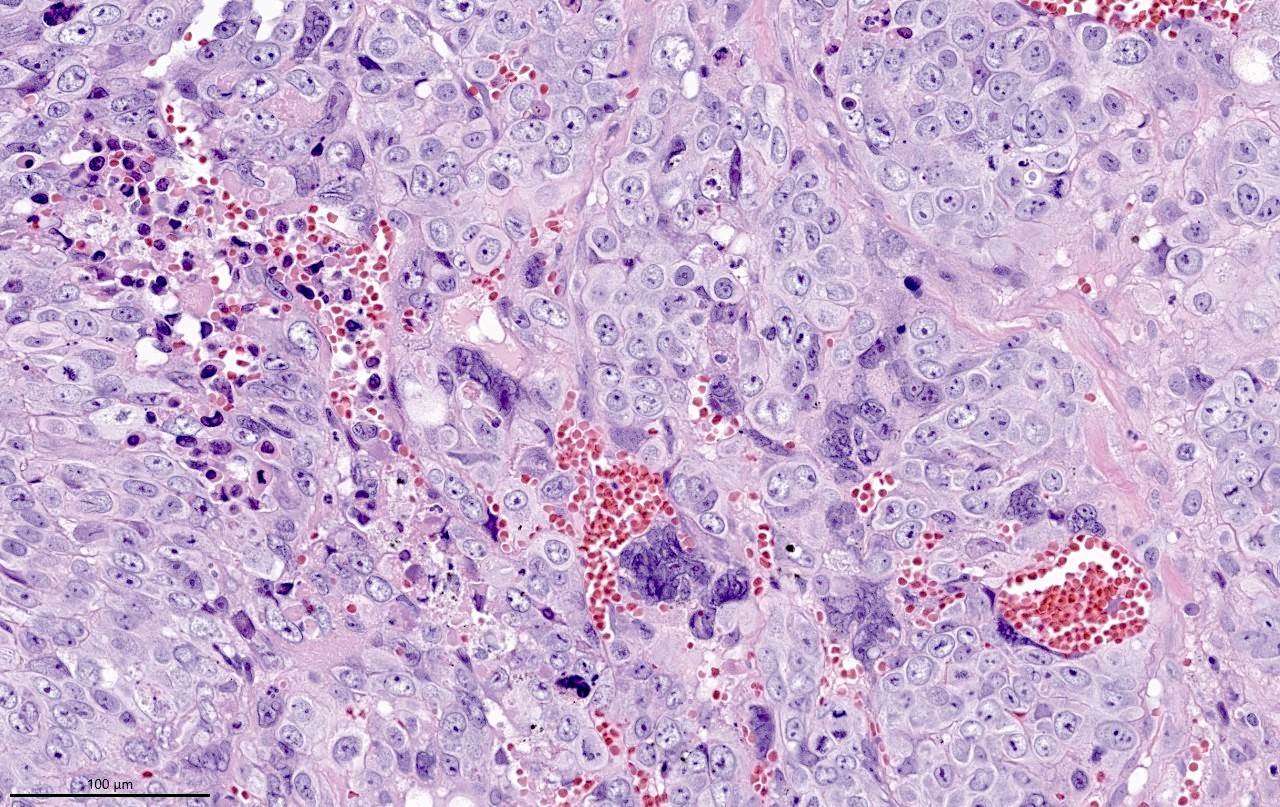

- Wide spectrum of trophoblastic differentiation, ranging from scattered isolated cells with trophoblastic differentiation to pure choriocarcinoma

- Often admixed with conventional urothelial carcinoma or other variants / subtypes

- When present as scattered isolated cells, they can be in the form of cytotrophoblasts (usually indistinguishable from high grade urothelial carcinoma or syncytiotrophoblast (recognizable by their multinucleated giant cells)

- Resembles choriocarcinoma in other organs

Microscopic (histologic) images